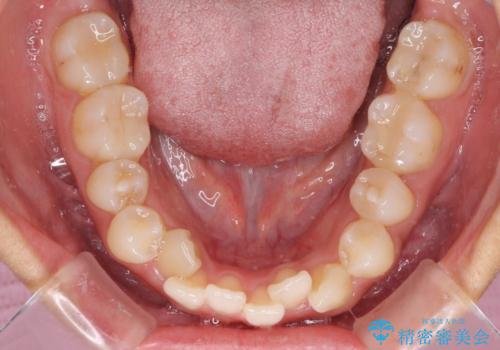

- 八重歯や前歯のデコボコを気にして来院された患者様です。

目立たない装置を希望されたので、上顎が裏側装置のハーフリンガルを選択し、上下左右の小臼歯(計4歯)を抜歯して矯正治療を行うこととしました。

補助装置を併用することで、八重歯を速やかに改善し、治療期間の短縮を図ることとしました。